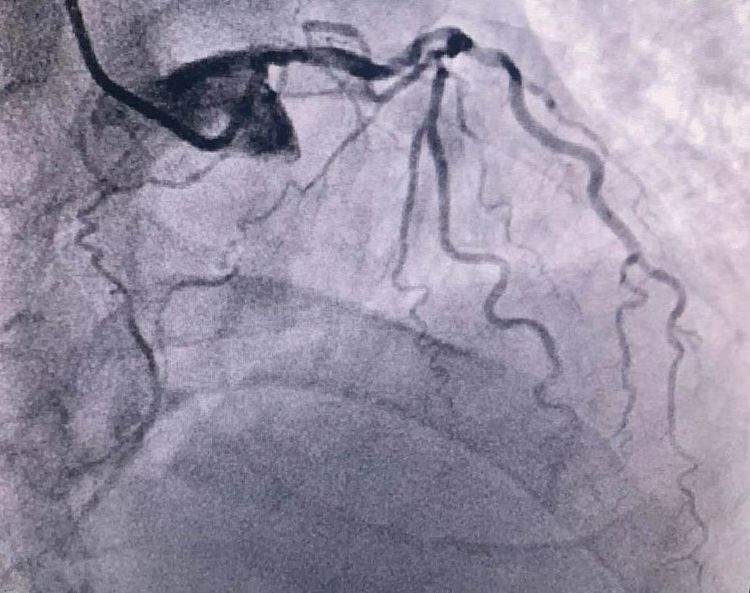

患者前降支、右冠100%閉塞,LCX中段60%狹窄。命懸一線,手術(shù)臺(tái)上持續(xù)胸痛。和患者家屬及時(shí)溝通后,決定行PTCA術(shù)。血壓低至60/40mmHg,在主動(dòng)脈內(nèi)球囊反博的支持下緊急行PCI術(shù)。軌道很快建立,導(dǎo)絲也及時(shí)通過病變血管,噩夢來了,患者發(fā)生室顫了。在吳棟梁院長的指揮下,李陽主任和心臟團(tuán)隊(duì)的成員共同努力下,除顫、冠脈內(nèi)溶栓、多個(gè)球囊輪流上陣,患者病情平穩(wěn)了,罪犯血管及時(shí)開通,血流恢復(fù)三級(jí)血流。平安下臺(tái),準(zhǔn)備擇日再處理冠脈情況。